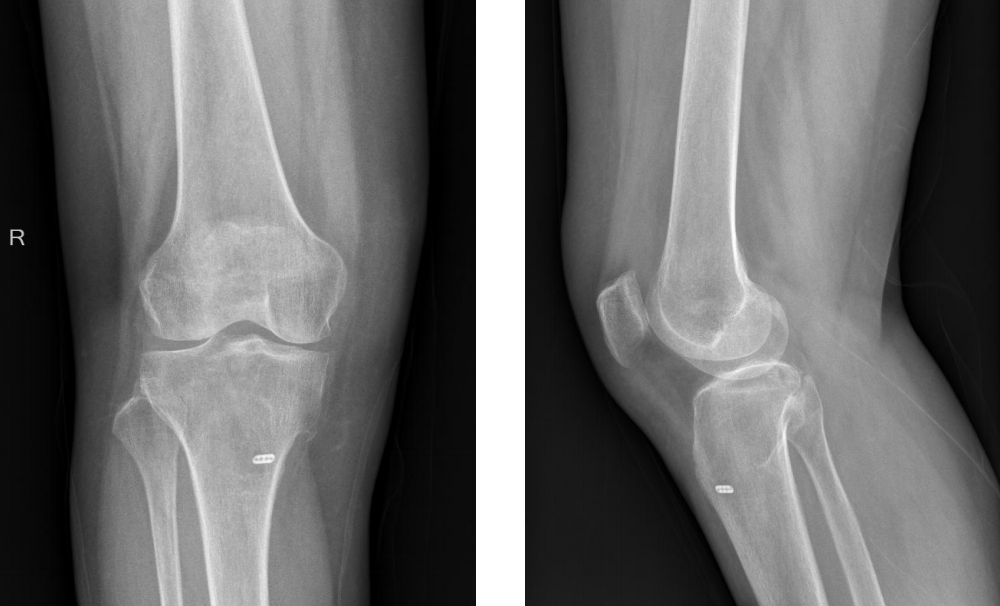

术后X线片

分型及术式